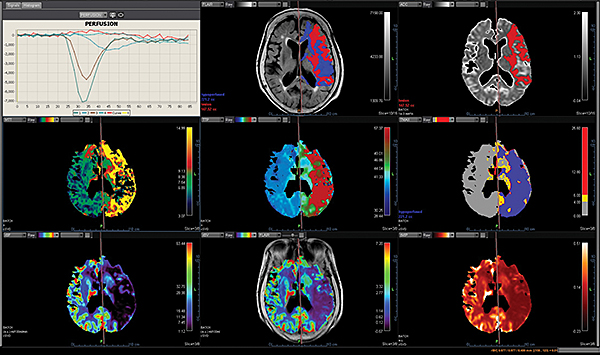

Перфузія DSC Perfusion

Додаток DSC Perfusion обчислює оптимізовані параметричні карти (rBV, rBF, TTP, MTT, TMAX, tMIP) із сирої перфузійної серії та забезпечує алгоритм для корекції ефектів розповсюдження контрастної речовини, обчислюючи карту проникності. Ця програма підтримує нерегулярний вибір часу та складається з наступних модулів: автоматична або ручна обробка arterial input function (функції артеріального наповнення), автоматична сегментація фону, чотири методи деконволюції (sSVD, cSVD, oSVD та байезівський) та алгоритм миттєвої корекції руху.

Додаток MR Neuro

Додаток Neuro інтегрований у розширену візуалізацію Vitrea і забезпечує спеціальні протоколи для пухлини мозку та розширені протоколи інсульту, які забезпечують швидку оцінку захворювань головного мозку.

Обчислює оптимізовані параметричні карти (rBV, rBF, TTP, MTT, TMAX, tMIP) із первинної перфузійної серії

Використовує автоматизований та настроюваний робочий процес

Включає повністю автоматизовану поетапну обробку для пацієнтів з пухлинами мозку, включаючи кількісний та якісний мультипараметричний аналіз

Забезпечує корекцію витоку контрасту та створення карти K2 rBV